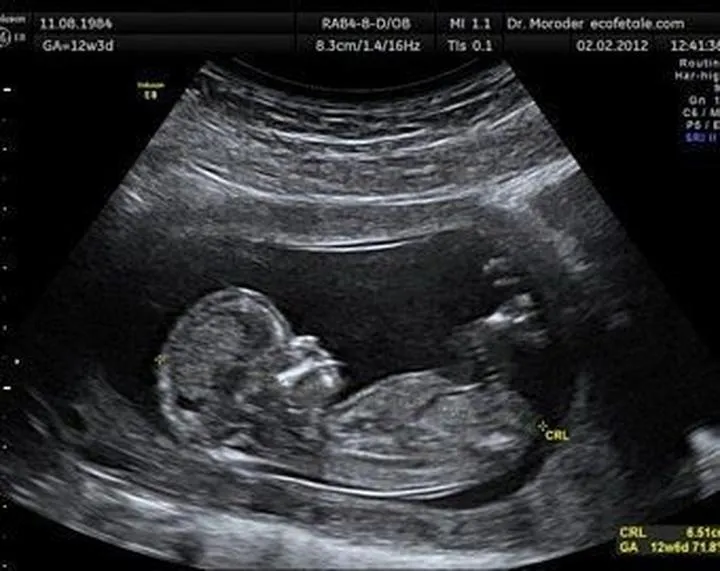

Gdy już zgubimy się w zawirowaniach dat, wówczas przychodzi czas na badanie USG, które uznaje się za znacznie dokładniejsze. Specjaliści wykonujący ultrasonografię zmierzą długość ciemieniowo-siedzeniową płodu, znaną jako CRL. To właśnie wcześniejsze USG pozwala na zminimalizowanie błędów. W idealnym scenariuszu warto przeprowadzić to badanie przed 10. tygodniem ciąży, gdy maluchy rosną w dość jednolitym tempie. Jednak jak to zwykle bywa, im później wykonasz USG, tym więcej problemów, ponieważ każde dziecko może rozwijać się w różnym tempie. Możemy zauważyć, że jedno dziecko znajduje się na innym etapie rozwoju niż drugie. Dlatego lekarze porównują dane z USG z datą miesiączki, co niejednokrotnie wywołuje zawrót głowy u przyszłych mam.

Dokładność pomiaru w badaniach USG zasługuje na chwilę uwagi, przede wszystkim dlatego, że każdy z nas pragnie mieć precyzyjne wyniki, zwłaszcza gdy zbliża się wyczekiwana data narodzin malucha. Kluczowym czynnikiem wpływającym na dokładność pomiarów jest moment, w którym przeprowadzamy badanie. Generalnie, im wcześniej w ciąży wykonamy USG, tym skuteczniej oceniamy rozwój płodu. W pierwszym trymestrze dzieci rozwijają się w zaskakująco zharmonizowany sposób, co sprawia, że pomiary są bardziej wiarygodne. Z każdą upływającą chwilą, stają się większe szanse na różnice, ponieważ każde dziecko rozwija się w swoim własnym tempie – jeden może przypominać małego pączka, a inny wręcz cukierka w paczce!

Drugim istotnym czynnikiem są dane, które lekarz analizuje. Pomiar długości ciemieniowo-siedzeniowej (CRL) stanowi klucz do oszacowania wieku płodu na początku ciąży, jednak w miarę jak maluszek rośnie, zaczynają mieć znaczenie inne parametry, takie jak dwuciemieniowy wymiar główki (BPD) czy długość kości udowej (FL). Oczywiście można się dziwić, że im więcej maluchy rosną, tym więcej parametrów trzeba mierzyć! W tym momencie wkrada się mały chaos, ponieważ niektóre dzieci mogą mieć długie nogi, podczas gdy inne mogą nieco odstawać od normy. Te różnice mogą prowadzić do tzw. „spóźnionych” pomiarów, co z kolei generuje nieporozumienia w określeniu terminu porodu.

W związku z tym, co na ten temat mówi nauka? Lekarze opierają swoje argumenty dotyczące USG głównie na pomiarach, takich jak długość ciemieniowo-siedzeniowa (CRL), której dokładność jest najwyższa w pierwszym trymestrze. Po tym okresie terminy porodu mogą się znacznie różnić, a tempo wzrostu płodu staje się bardziej nieprzewidywalne. Lekarze twierdzą, że jeżeli różnica nie przekracza sześciu dni, sytuacja jest w porządku. Natomiast, gdy zaczynamy rozmawiać o różnicach tygodniowych, to sprawy mogą się skomplikować. Mamusia w takiej sytuacji ma prawo czuć się zdezorientowana, lecz warto pamiętać, że przynajmniej zyskuje szansę na przedsmak bycia matką – to z pewnością ekscytujące, prawda?